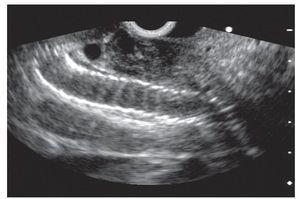

A linear array echoendoscope (GF-UCT140, Olympus America, Center Valley, PA, USA) was placed in the duodenal bulb region allowing visualization of a dilated common bile duct and a distal occluded biliary metallic stent (Figure 1).

¿ Figure 1. EUS showing biliary metallic stent occluded at the distal portion and head of the pancreas.